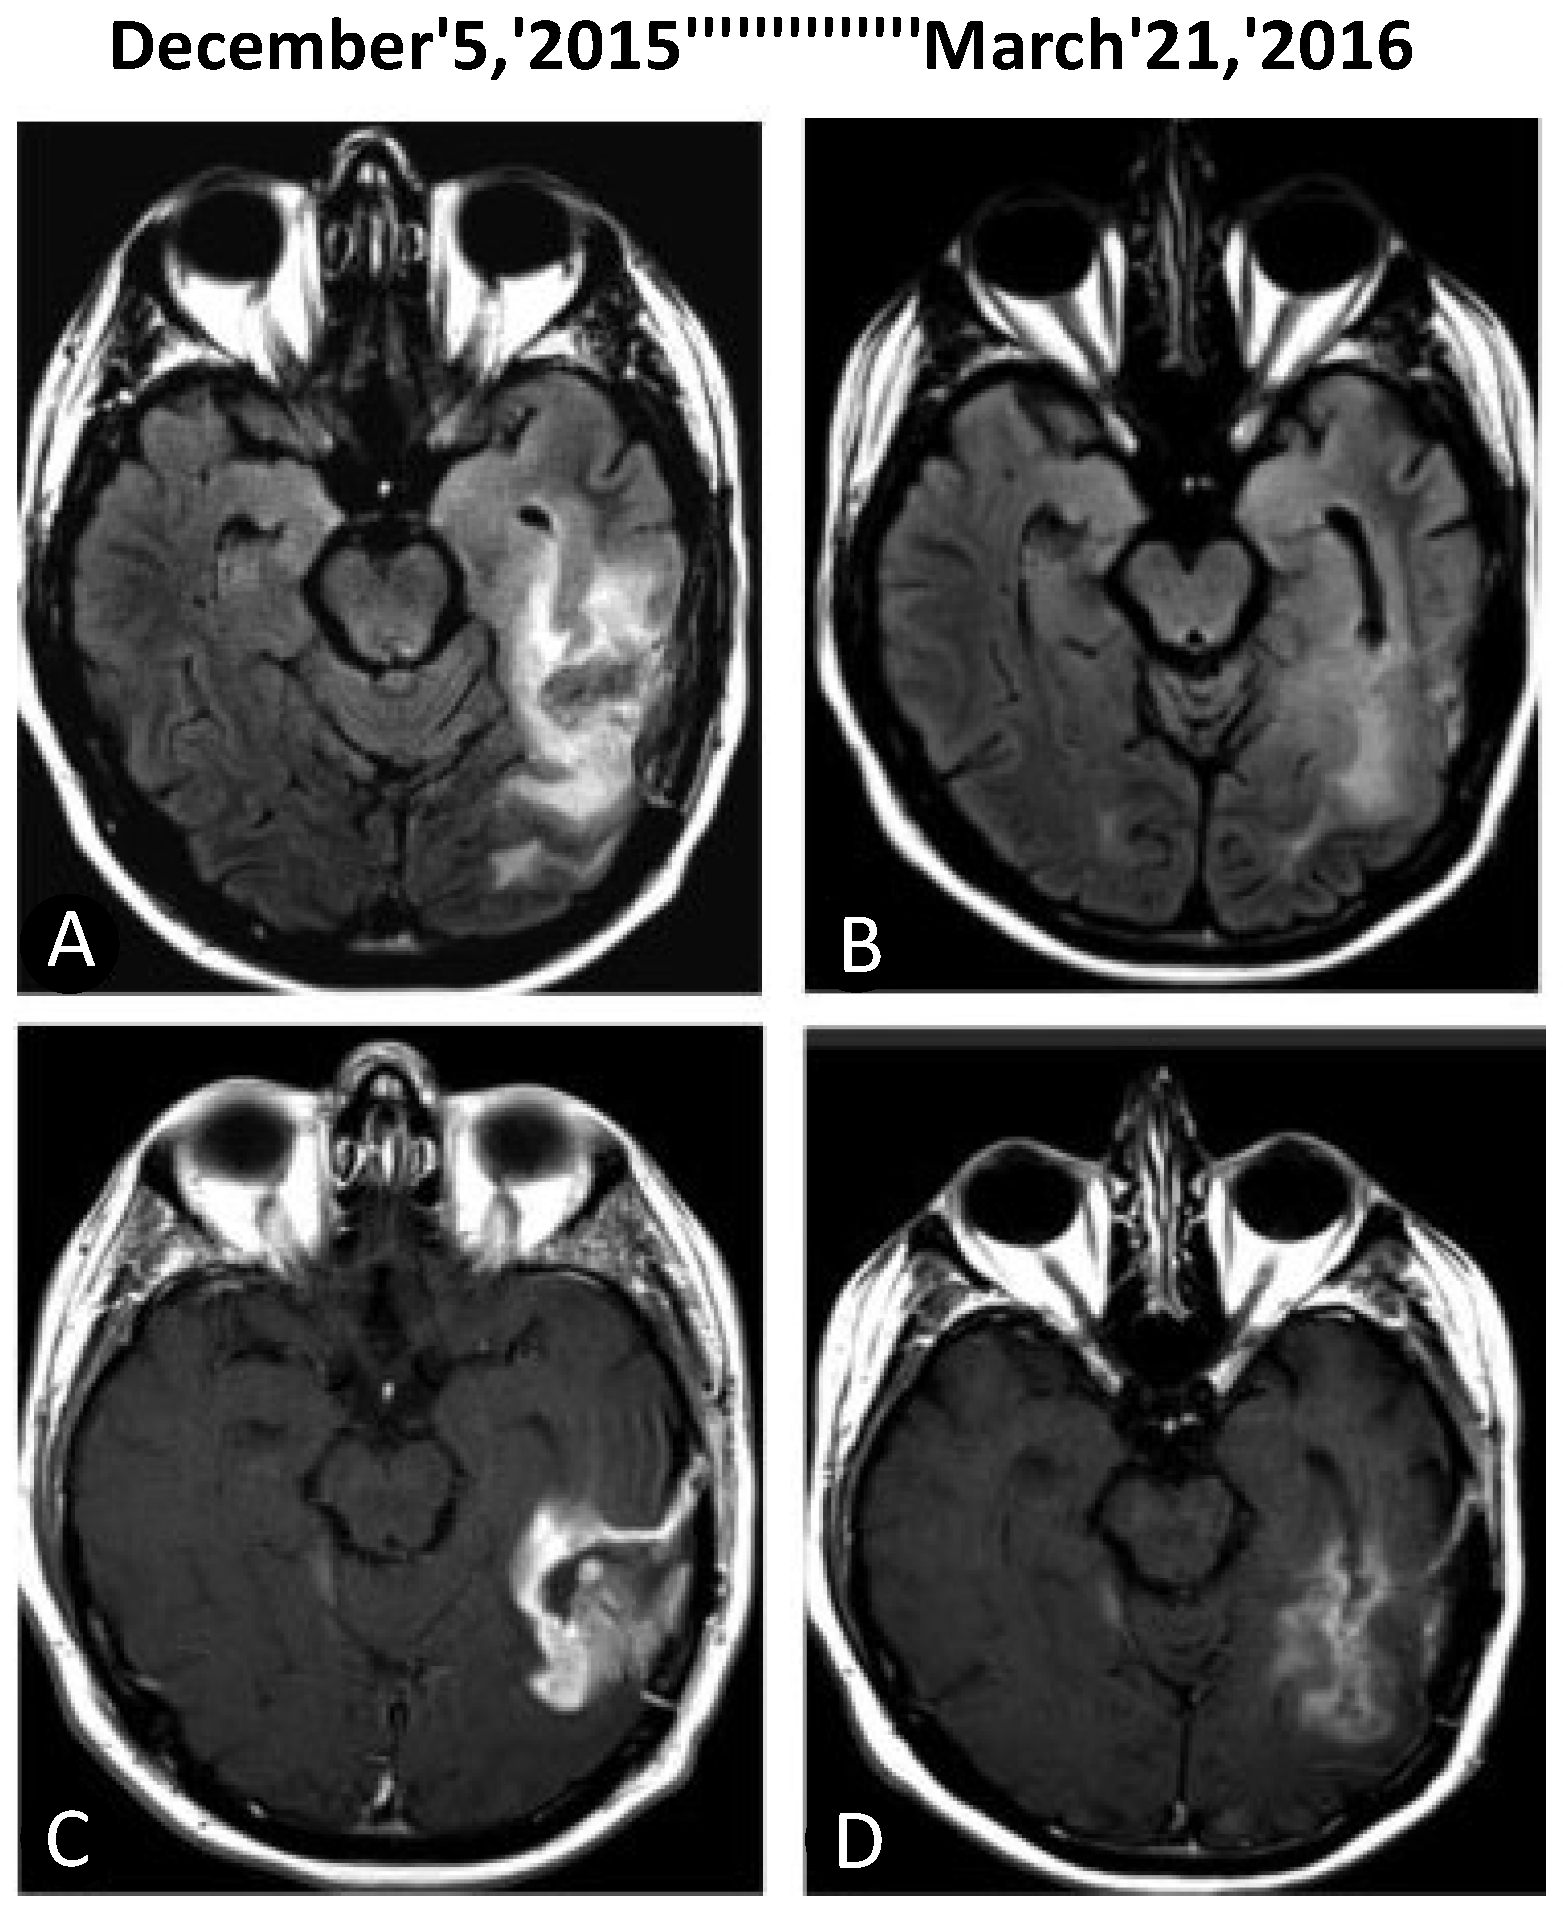

- Santos, J.G.; Da Cruz, W.M.S.; Schönthal, A.H.; Salazar, M.D.; Fontes, C.A.P.; Quirico-Santos, T.; Da Fonseca, C.O. Patient with recurrent glioblastoma responding favorably to ketogenic diet combined with intranasal delivery of perillyl alcohol: A case report and Literature Review. Arq. Bras. Neurocir. 2017, 36, 194–199. [Google Scholar] [CrossRef]

- Santos, J.G.; Da Cruz, W.M.S.; Schonthal, A.H.; Salazar, M.D.; Fontes, C.A.P.; Quirico-Santos, T.; Da Fonseca, C.O. Efficacy of a ketogenic diet with concomitant intranasal perillyl alcohol as a novel strategy for the therapy of recurrent glioblastoma. Oncol. Lett. 2018, 15, 1263–1270. [Google Scholar] [CrossRef]